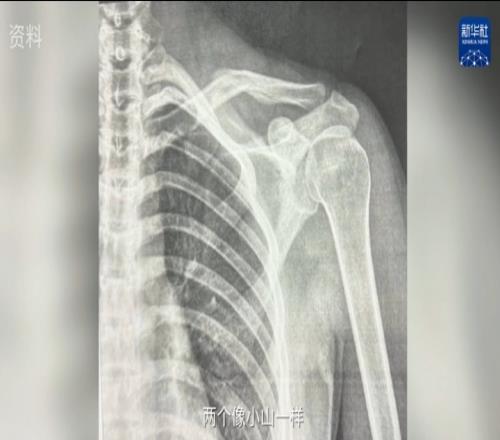

完了以后不是有亞冬會嘛,我就是又太早上雪了。我那次摔的時候就鎖骨斷了。其實這個是鎖骨第二次斷,你如果有直接的光對著它,你能看見兩個像小山一樣長在骨頭上。還好不需要做手術。所以我就是養它養了大概3個月。”